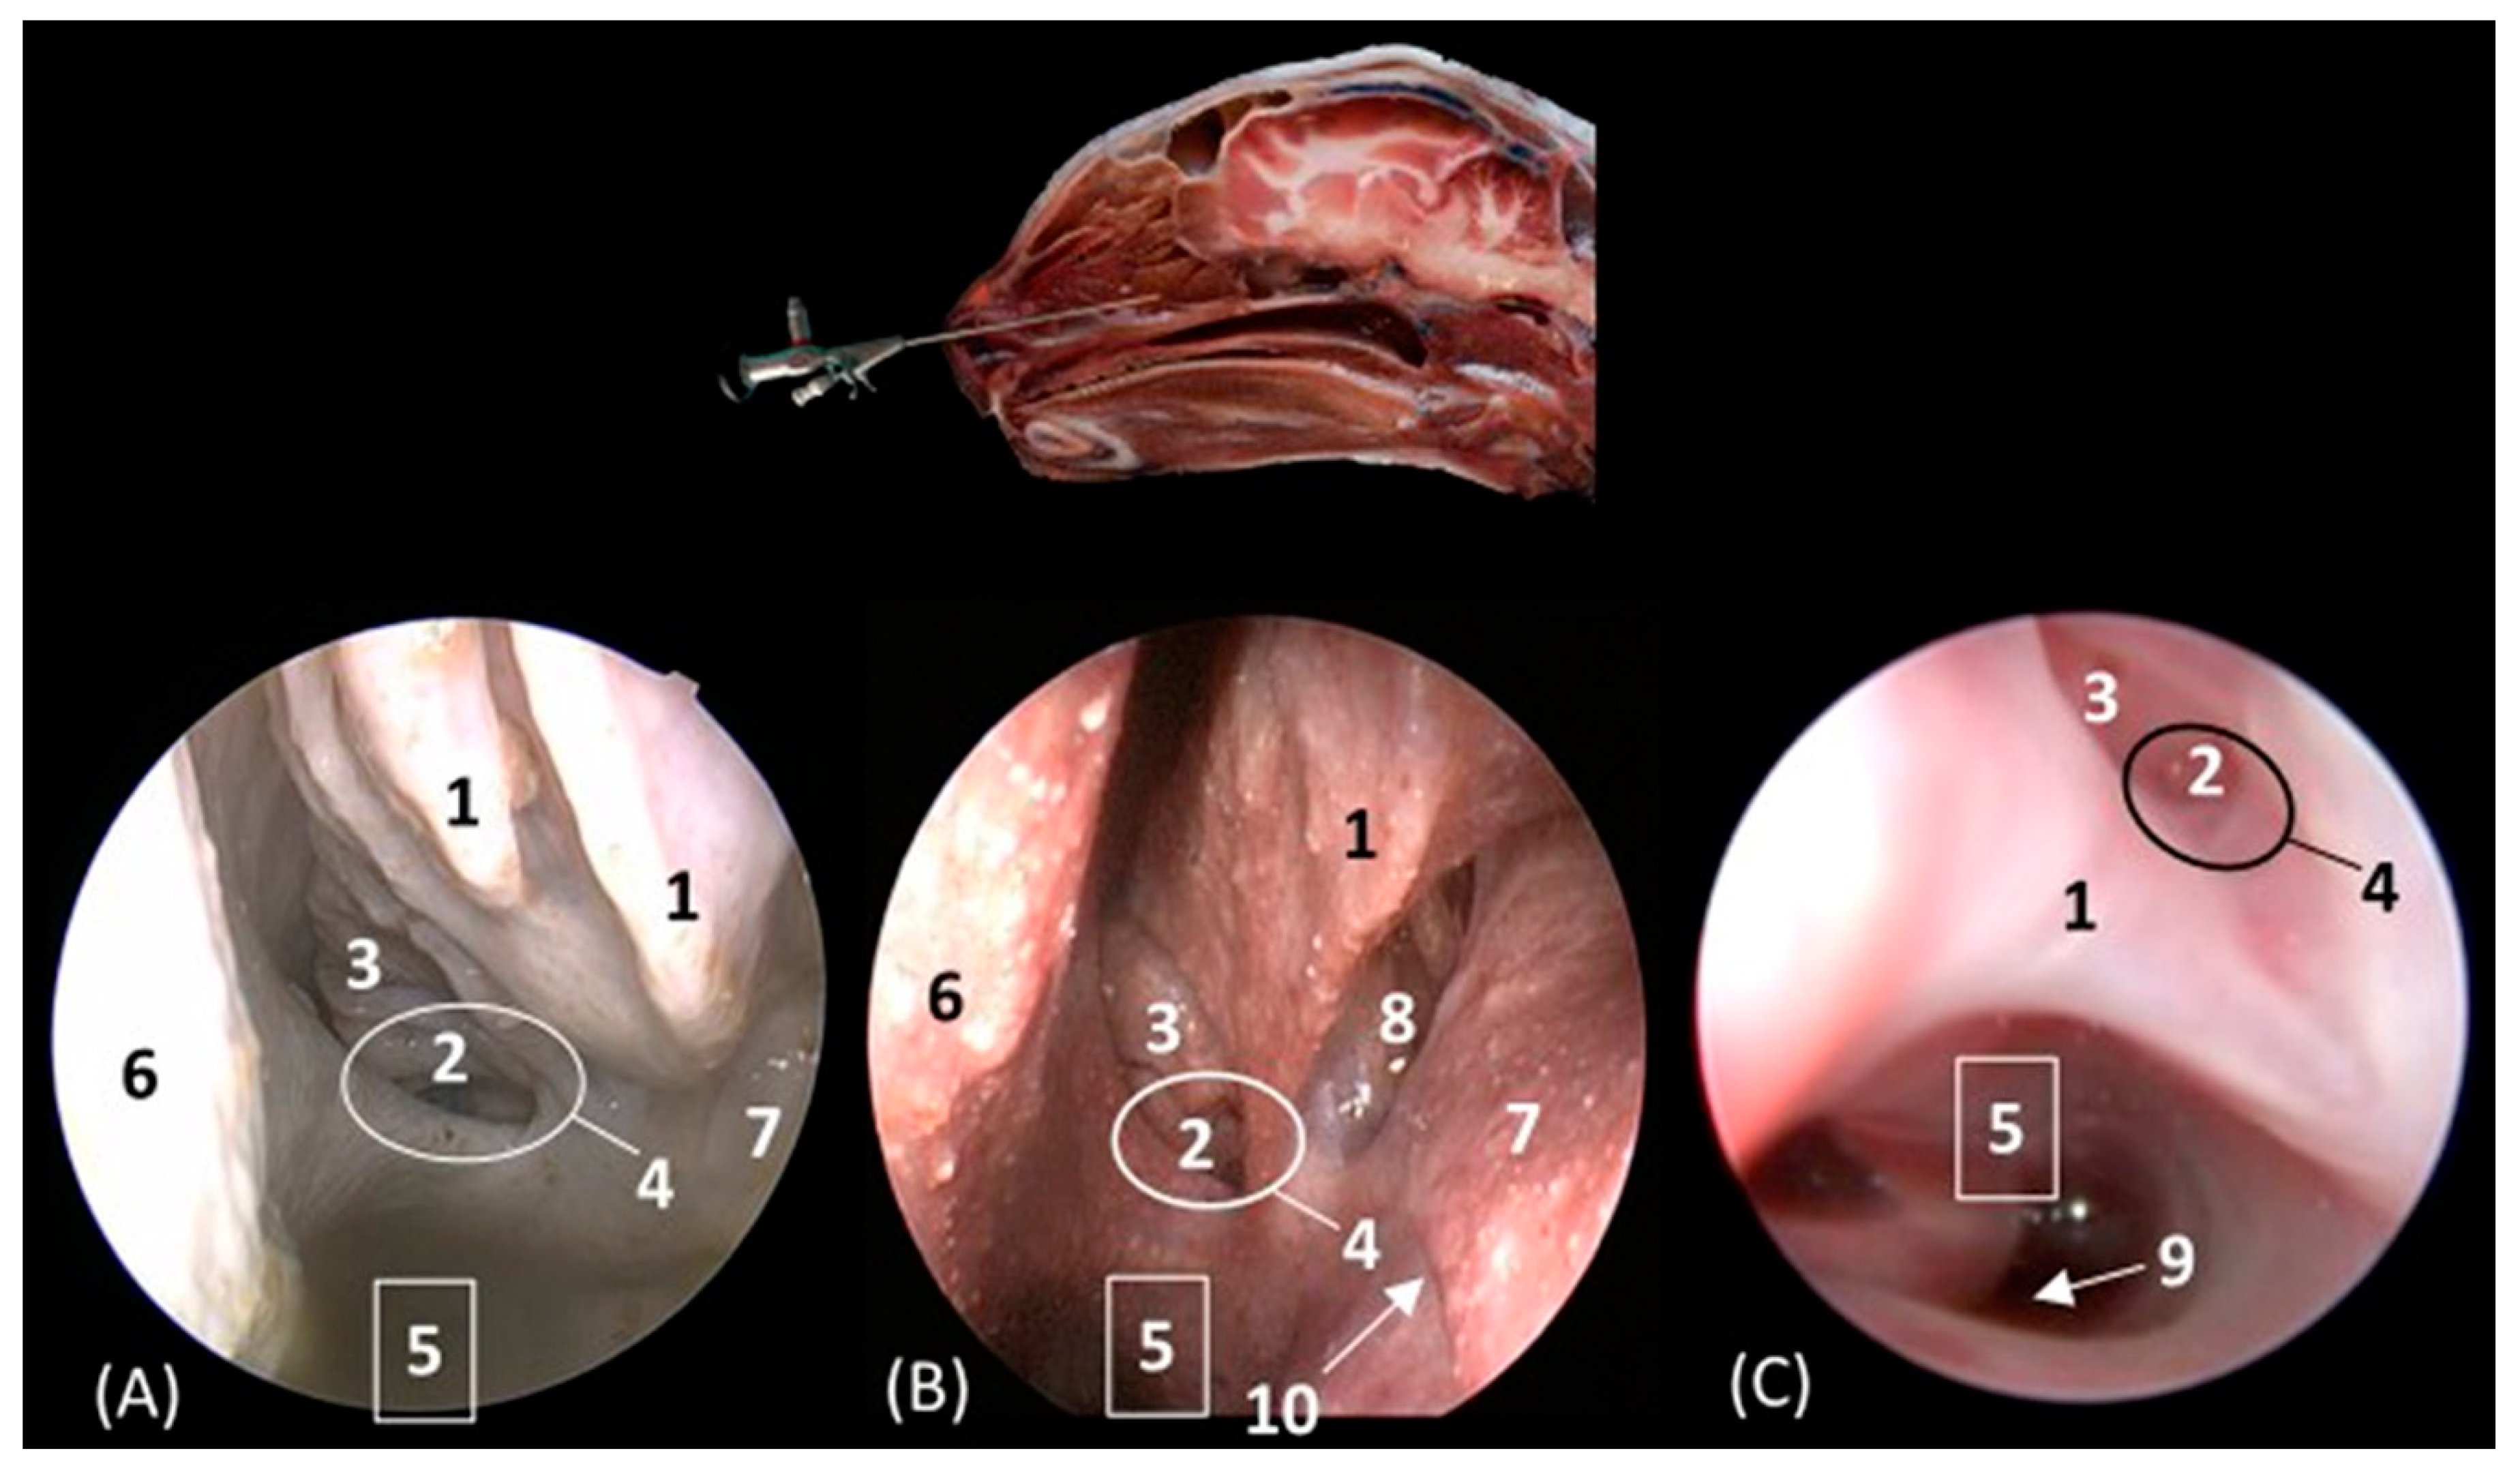

Figure 16A–C represent a more caudal view at the level of the ethmoidal labyrinth. Only views of the lion, cheetah, and cat are included, as due to the rigidity of the fixed structures of the nasal cavity of the leopard, access by rhinoscopy for a more caudal study of the nasal cavity is presented. In this section, the third and fourth endoturbinates were identified, as well as the opening of the sphenoid sinus, which is close to the floor of the nasal cavity. In the cat, the nasopharyngeal or choanal opening can also be identified ventrally, and in the cheetah, the pharyngeal orifice of the auditory tube can be identified on the lateral wall of the nasal cavity, ventral to the third and fourth endoturbinates.

Figure 16. Endoscopic images of the nasal cavity at the level of the ethmoidal labyrinth. The level of this endoscopic study is shown above in the sagittal anatomical section. Images are observed so that the right side of the head is to the left of the image. (A): Lion; (B): cheetah; and (C): cat. 1. Ventral nasal concha; 2. 4th endoturbinate; 3. 3rd endoturbinate; 4. opening of the sphenoidal sinus; 5. ventral nasal meatus; 6. nasal septum; 7. nasal cavity: lateral wall; 8. lateral nasal gland; 9. choana; 10. pharyngeal orifice of the auditory tube.

The pharyngeal orifice of the auditory tube can be identified in more detail in Figure 17C, located on the lateral wall. The leopard is the only species where the orifice of the lateral nasal gland was identified, being located close to the straight fold and, more specifically, in the oblique fold (Figure 17A).

Figure 17. Endoscopic images of the nasal cavity showing the aperture of the lateral nasal gland duct, frontal opening, and pharyngeal orifice of the auditory tube (observed only in big cats). The levels of this endoscopic study are shown above in the sagittal anatomical sections. Images are observed so that the right side of the head is to the left of the image. (A): Leopard; (B): lion; and (C): cheetah. 1. Nasal septum; 2. nasal cavity: lateral wall; 3. pharyngeal orifice of the auditory tube; 4. straight fold; 5. dorsal nasal meatus; 6. dorsal nasal concha; 7. frontal opening; 8. nasal cavity: roof; 9. alar fold; 10. ventral nasal concha; 11. nasal cavity: floor; 12. oblique fold; 13. aperture of the lateral nasal gland duct.

Below, Figure 18A–C detail the nasopharyngeal or choanal opening in the lion, cheetah, and cat on the floor of the nasal cavity, showing the soft palate at this level. In this view, we can also see the pharyngeal opening of the auditory tube on the lateral wall of the nasal cavity.

Figure 18. Endoscopic images at the level of the choana and nasopharynx. The level of this endoscopic study is shown above in the sagittal anatomical section. Images are observed so that the right side of the head is to the left of the image. (A): Lion; (B): cheetah; and (C): cat. 1. Presphenoid bone; 2. nasal septum; 3. nasal cavity: lateral wall; 4. choana; 5. nasal cavity: floor; 6. pharyngeal orifice of the auditory tube; 7. soft palate; 8. palatine aponeurosis.